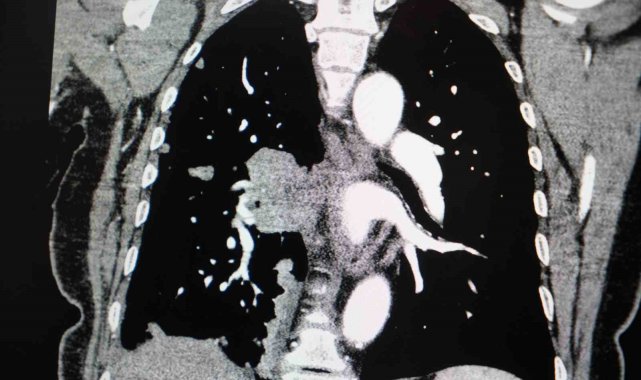

Göğüs Hastalıkları Uzmanı Prof. Dr. Şevket Özkaya, Türkiye'de sigara kullanımının özellikle kadınlar arasında alarm verici boyutlara ulaştığını söyledi. Özkaya, "Kadınlardaki sigara kullanımı artışı Cumhuriyet tarihinin rekor seviyesindedir" dedi.9 Şubat Sigarayı Bırakma Günü dolayısıyla değerlendirmelerde bulunan Prof. Dr. Özkaya, "2012 ile 2022 yılları arasındaki verilere baktığımızda, ülkemizde sigara içme oranı genel olarak yüzde 20 arttı. Erkeklerde bu artış yüzde 12 düzeyindeyken, kadınlarda yüzde 38 gibi çok ciddi bir artış söz konusudur. Bugün erkeklerin yüzde 45'i, kadınların ise yüzde 19'u sigara içiyor. Özellikle 35-44 yaş grubundaki kadınlarda tütün kullanımı Cumhuriyet tarihinin en yüksek seviyelerine ulaştı. Bu yaş grubunda her dört kadından biri sigara içiyor" dedi."Sigara kullanımının artması, gençlerde ve çocuklarda sigarayla temas riskini de artıracak"Kadınlarda sigara bağımlılığının artmasının toplumsal sonuçları olduğuna vurgu yapan Prof. Dr. Özkaya, "Kadın, anne figürü toplumda önemli bir rol modeldir. Kadınlarda sigara kullanımının artması, gençlerde ve çocuklarda sigarayla temas riskini de artıracaktır. İkinci önemli sorun ise kadınların sigarayı bırakmasının erkeklere göre daha zor olmasıdır. Bırakma oranları erkeklerin gerisinde seyrediyor" şeklinde konuştu."Kadınlarda akciğer kanseri vakaları belirgin şekilde artıyor"Akciğer kanseri vakalarındaki artışa da dikkat çeken Özkaya, "Son yıllarda hem sigara içen hem de hiç sigara kullanmamış bireylerde akciğer kanseri vakalarında dikkat çekici bir artış görüyoruz. Özellikle kadınlarda adenokarsinom tipi akciğer kanseri belirgin şekilde artış göstermektedir., Yapılan son araştırmalara göre akciğer kanseri teşhislerinin yaklaşık yüzde 20'si hiç sigara içmemiş bireylerde konuluyor. Bunun en önemli nedeni pasif içiciliktir. Yani siz sigara içmeseniz bile, yakın çevrenizde sigara içiliyorsa akciğer kanseri riskiyle karşı karşıya kalabilirsiniz" ifadelerini kullandı."Sigara kadınlarda kalp krizi ve cinsiyete özgü kanserleri de artırıyor"Sigaranın kadın sağlığı üzerindeki etkilerine değinen Prof. Dr. Özkaya, "Sigara kullanımı kadınlarda sadece akciğer kanseri riskini değil, kalp krizi riskini de ciddi şekilde artırmaktadır. Ayrıca gebelikle ilgili sorunlar, bebek sağlığı problemleri ve rahim ağzı kanseri gibi cinsiyete özgü hastalıklar da sigarayla doğrudan ilişkilidir" dedi.Özkaya sözlerini şöyle tamamladı:"Sigara içen kadınlarda, kanserle ilişkili bazı gen mutasyonlarını erkek içicilere göre daha sık görüyoruz. Bu nedenle kadınlarda sigara kullanımı, çok daha dikkatle ele alınması gereken önemli bir halk sağlığı sorunudur."